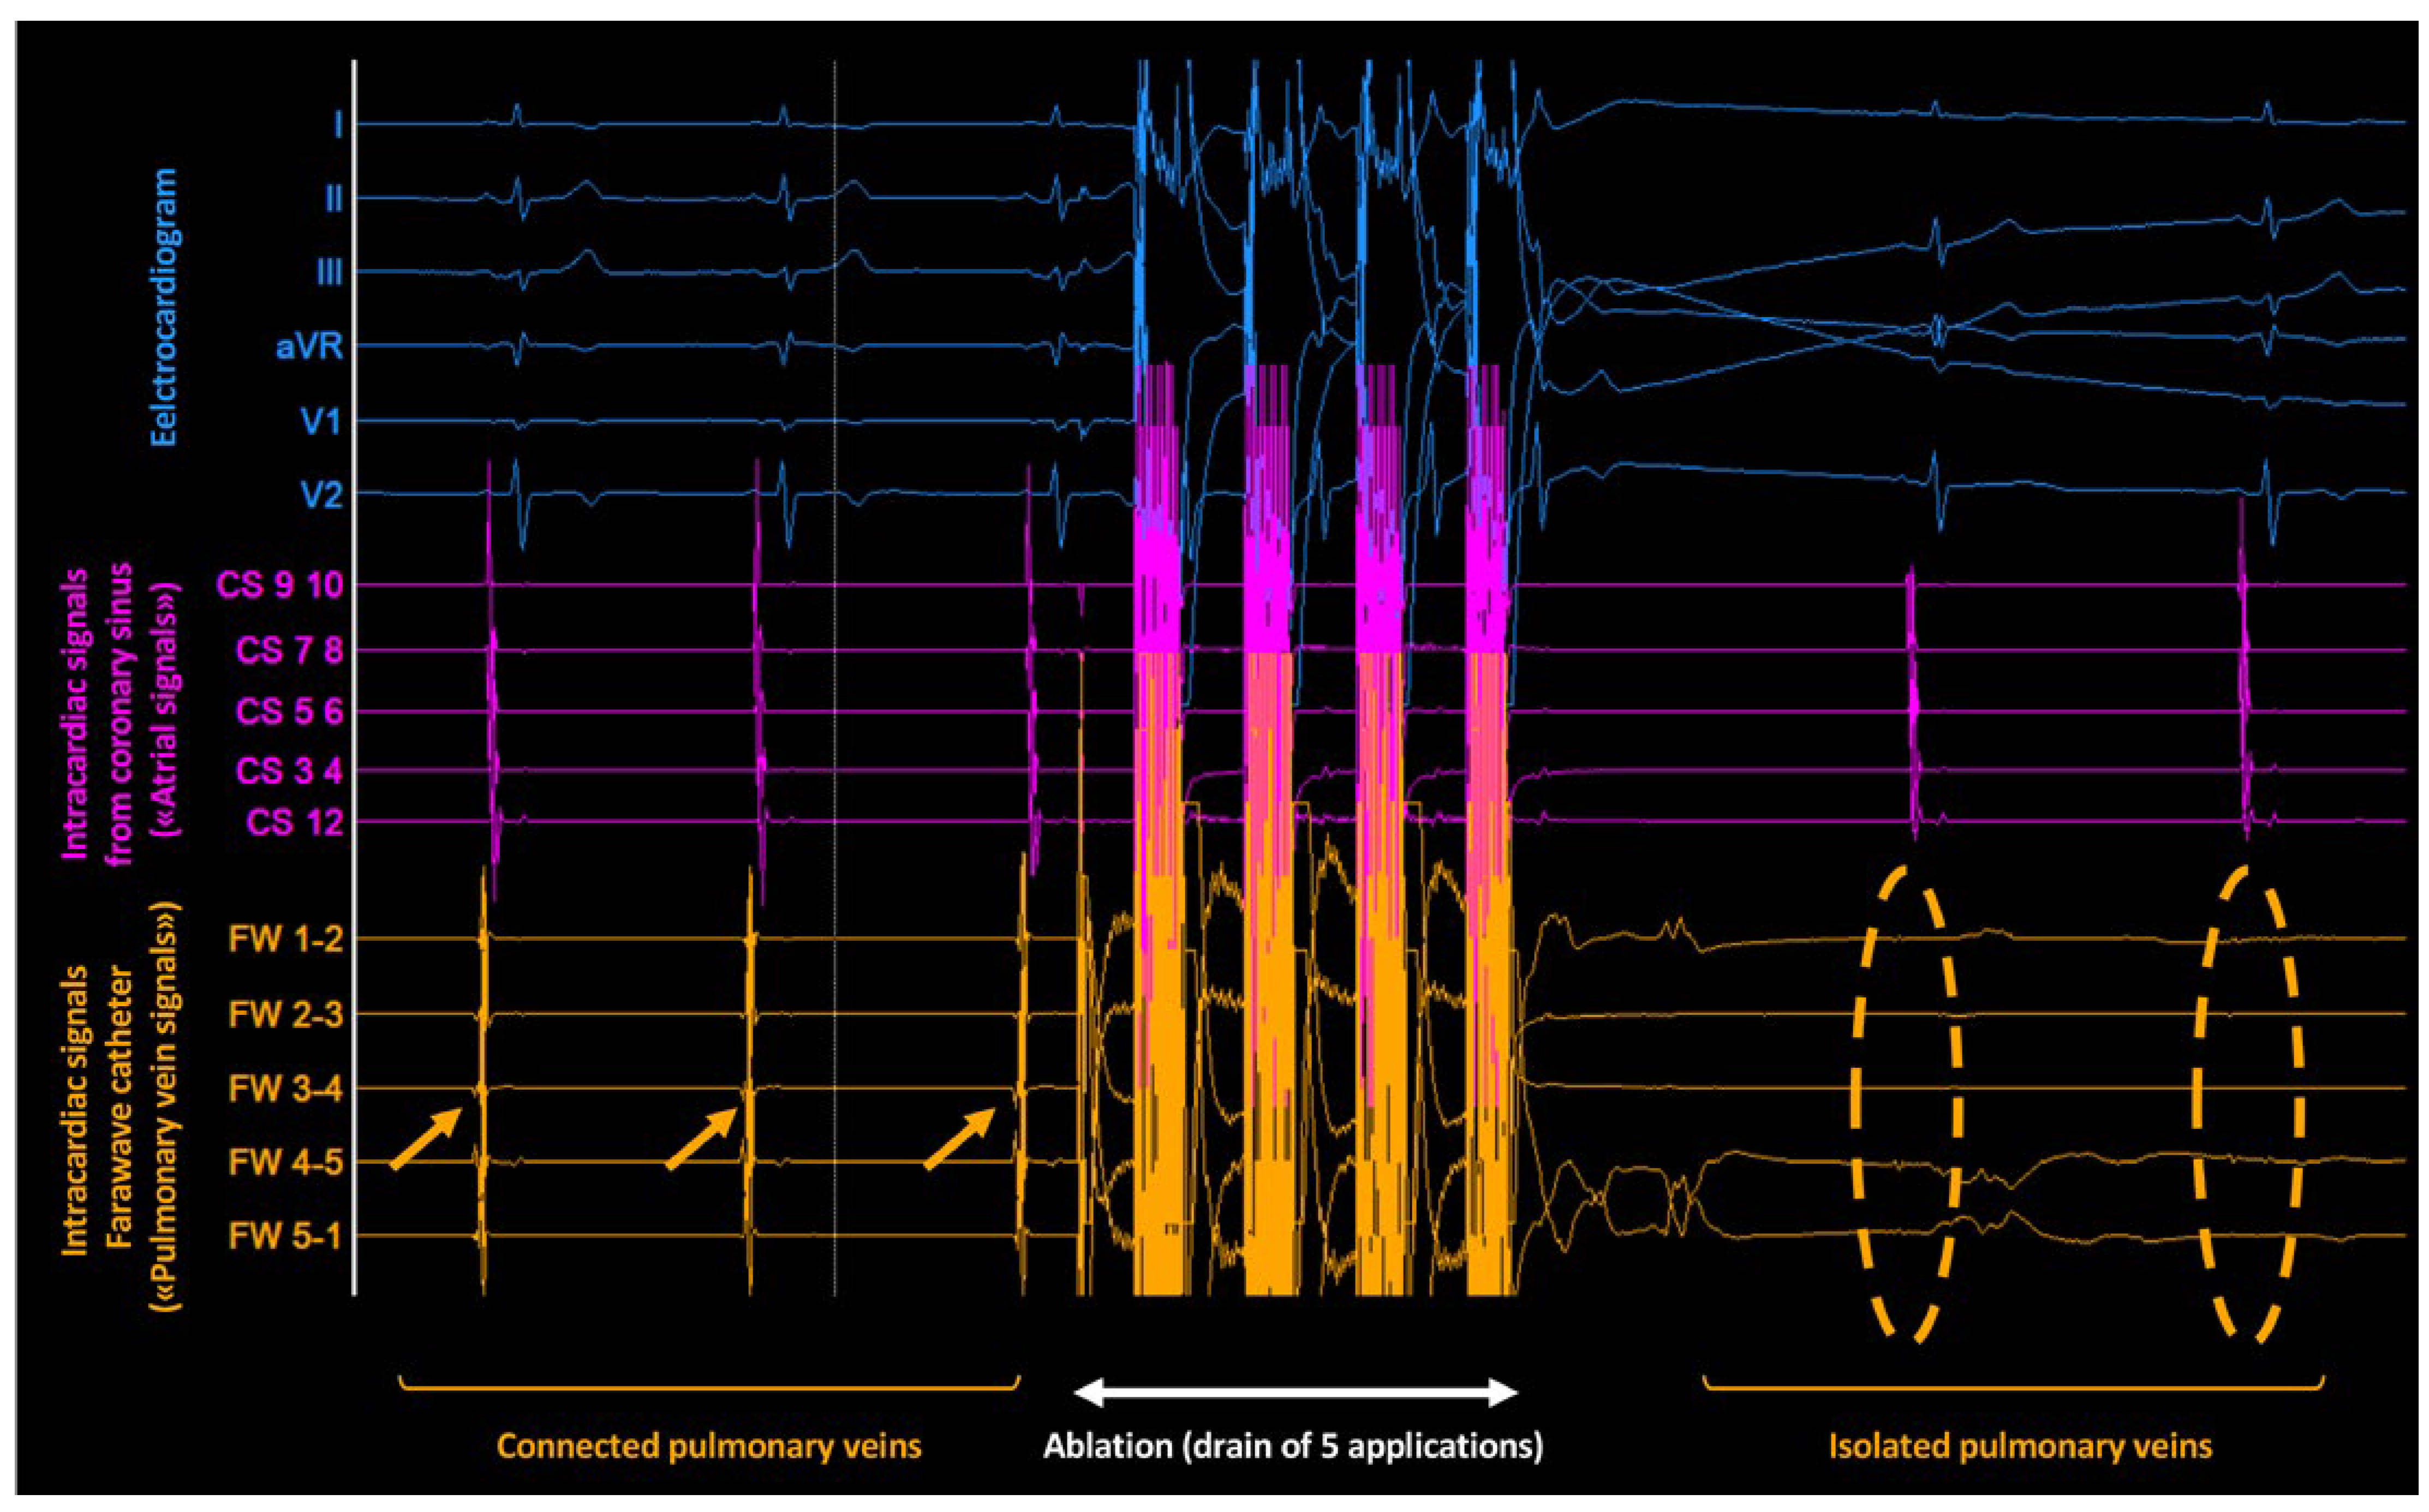

- Kueffer, T.; Baldinger, S.H.; Servatius, H.; Madaffari, A.; Seiler, J.; Mühl, A.; et al. Validation of a multipolar pulsed-field ablation catheter for endpoint assessment in pulmonary vein isolation procedures. Europace 2022, 24, 1248–1255. [Google Scholar] [CrossRef] [PubMed]